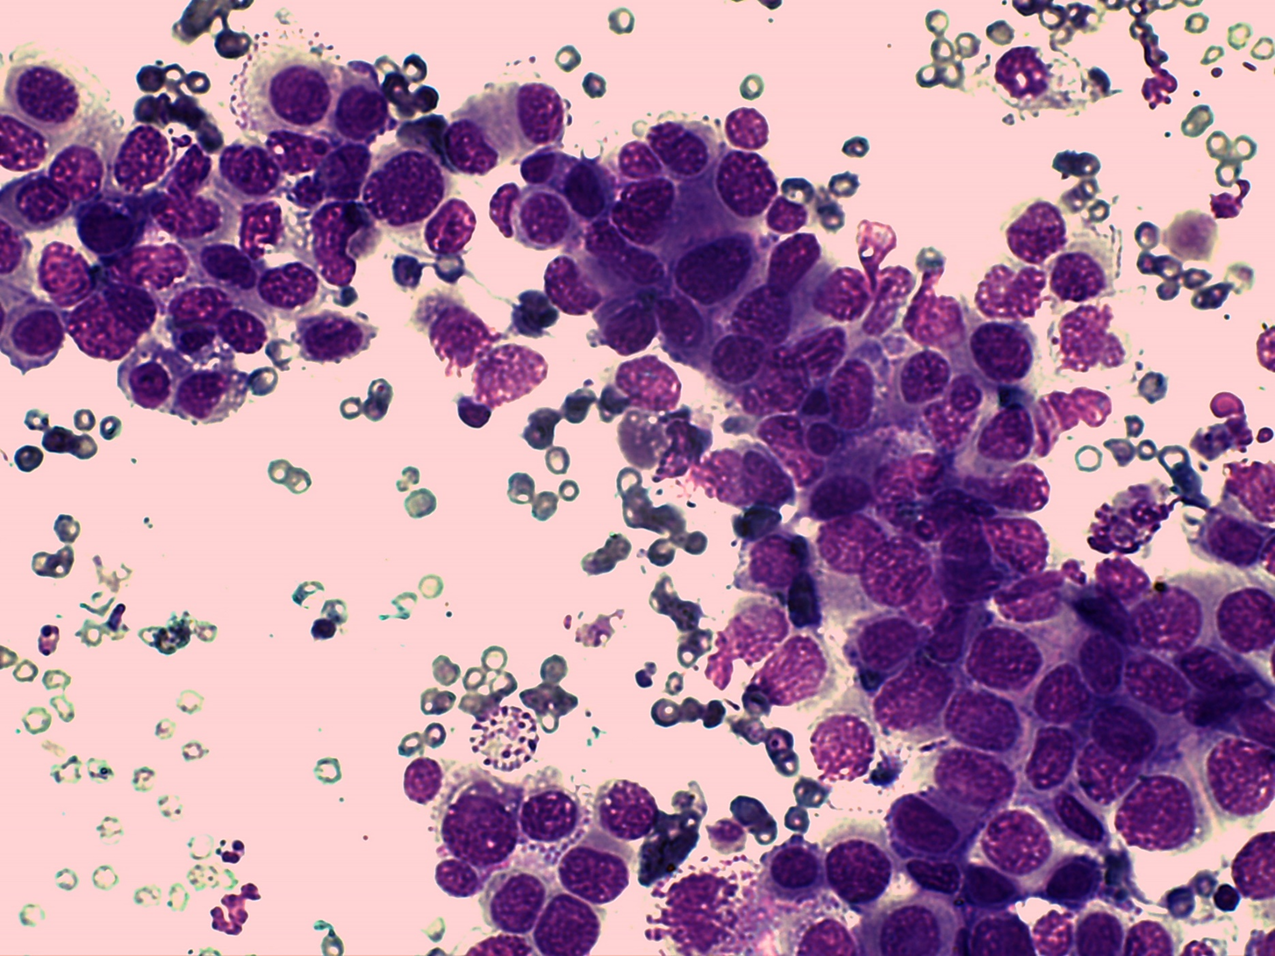

Describe round

§High yield, discrete round cells, not adherent

Examples of round neoplasia

§Lymphocytes

§Mast Cells

§Histiocytes

§Plasma cells

-Benign (histiocytoma)

-Malignant (Mast cell tumour)

Lymph node- lymphoma